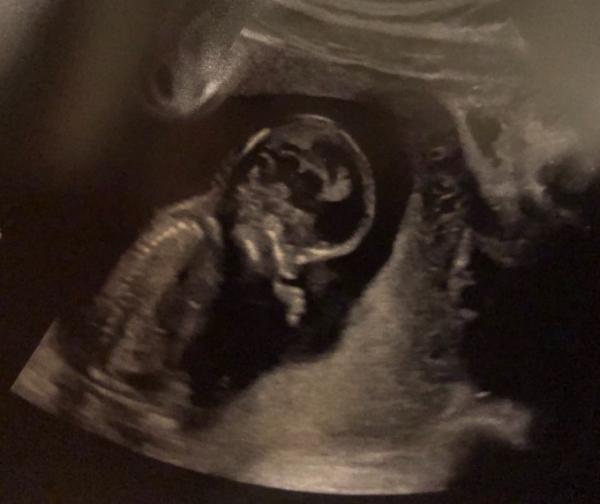

Hallo! Heute gab es beim FA 20 Minuten Baby Kino einschließlich Herztöne! Hatte Nackenfaltenmessung und es wollte alles zeigen außer zunächst den Nacken. Vom Ersteindruck scheint alles gut zu sein. Bin so erleichtert! SSL bei 12+6: 7,5 Bin 2 Tage weiter als der Plan. Nun 7-10 Tage auf Ergebnisse warten...

Bild zu Heute war Baby Kino! < 3 - Forum für März - Mamis